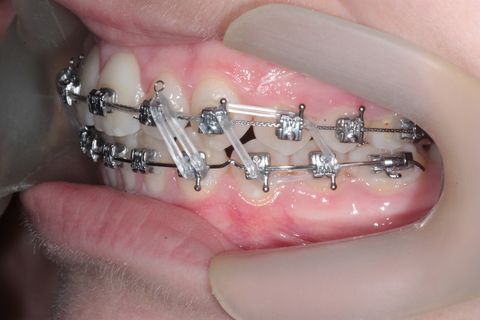

Fase final

Fase Final, intercuspidando e talvez haverá necessidade de desgastes interproximais devido a Bolton superior

Paciente Classe II, já havia usado disjuntor por falta de espaço, durante tratameto foi usado o Twin Force para projeção da arcada inferior e melhora do encaixe em Classe I de canino,na finalização do caso vemos que a paciente possui Bolton Superior o que provavelmente gerará a necessidade de desgastes interproximais para concluirmos com uma finalização adequada do caso.